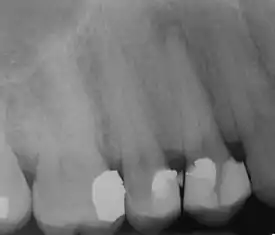

![]() | |

| Radiograph showing bone loss between the two roots of a tooth (black region). The spongy bone has receded due to infection under tooth, reducing the bony support for the tooth. | |